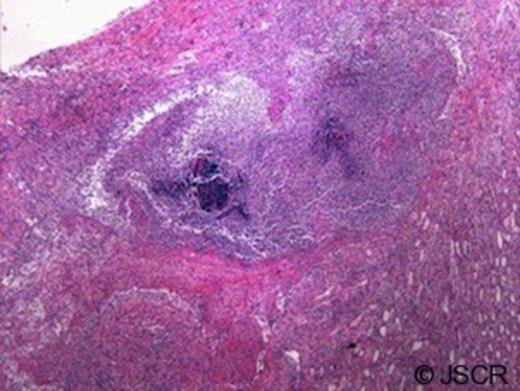

Pathologic examination of the removed kidney demonstrated active infection with bacteria and microabscess (Figure 3). In addition, the granulomatous and necrotising inflammation seemed to coalesce in a fistulous tract toward the renal capsular surface with a surrounding haematoma (Figure 4). Delayed review of the slides following the discovery of his HIV status demonstrated classic focal segmental glomerulosclerosis.

Cortex with necrosis, hemorrhage and fistulous tract (A) associated with capsular hematoma (B) (10x magnification)